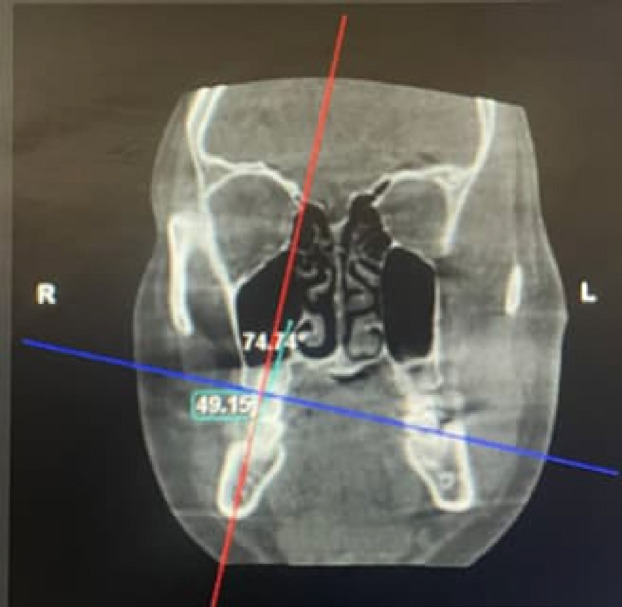

Material and methods: This retrospective study was conducted in the Department of Orthodontics and Dentofacial Orthopedics, Manipal College of Dental Sciences, Mangalore. The records of 126 subjects including skeletal class I subjects as the control group (n = 63) and skeletal class III patients as the experimental group (n = 63) were obtained. The tongue-to-palate distance of all the subjects was measured using the method described by Graber (Graber et al., 1997) on lateral cephalograms. CBCT images were standardized and acquired by keeping the patient's head in the natural position. Buccolingual inclinations were measured on CBCT coronal sections as the angle between the reference plane (line perpendicular to the line joining the buccal and lingual crest of the alveolar bone) and the long axis of each tooth. SPSS software, version 25.0 was used to perform the statistical analyses. To analyze the association between tongue posture and buccolingual inclination of teeth, the Pearson correlation coefficient was calculated, with a power of 80%.